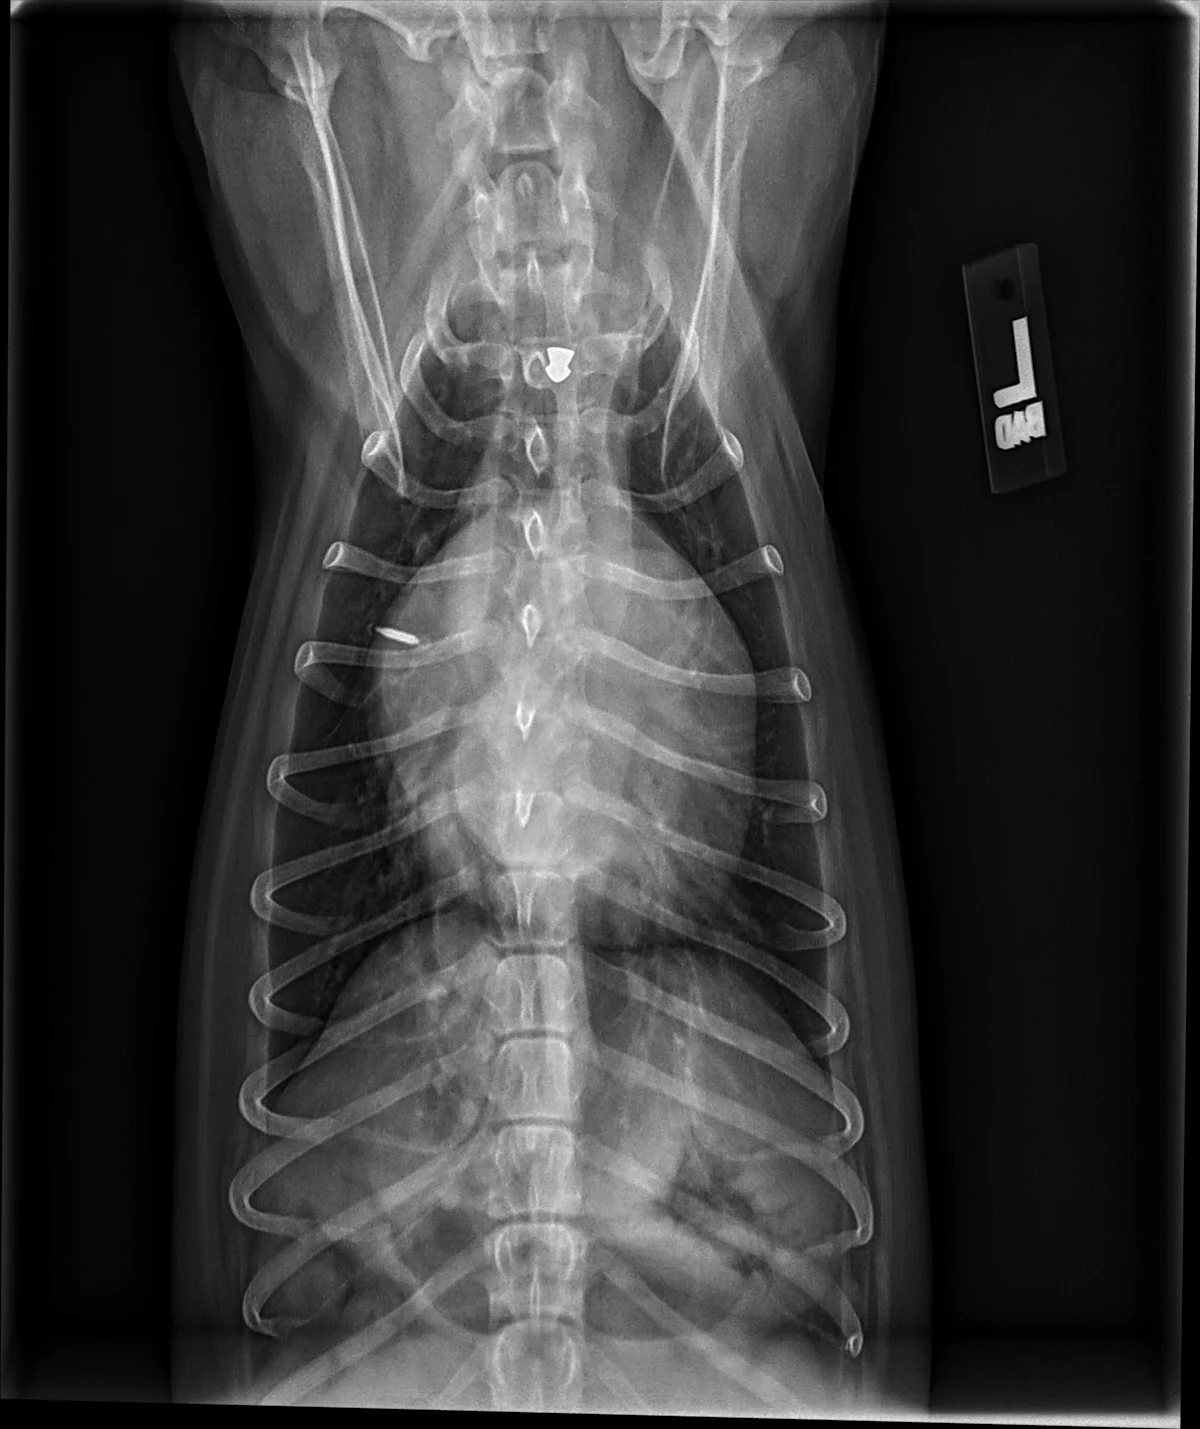

FIGURE 6 Right lateral and DV projections of 2 dogs with significant left-sided volume overload and heart enlargement secondary to MMVD. Moderate (A, B) and severe (C, D) changes can be seen. Dorsal elevation of the caudal portion of the trachea and mainstem bronchi secondary to heart enlargement, soft tissue opacity bulge in the region of the caudal waist representing the enlarged left atrium, and increased apicobasal length of the cardiac silhouette can be appreciated in the lateral views (B, D). Changes in the appearance of the borders of the left atrium and mainstem bronchi, as well as a visible auricular bulge in the DV view can be compared with those from a normal dog (Figures 1-3). An air gun ballistic (A, B) was also found incidentally. VHS, VLAS, M-VLAS, and VRHi collected from lateral view B are 11.4, 2.5, 4, and 3.6, respectively, and 12.7, 3.4, 5.9, and 4.1, respectively, collected from lateral view D.